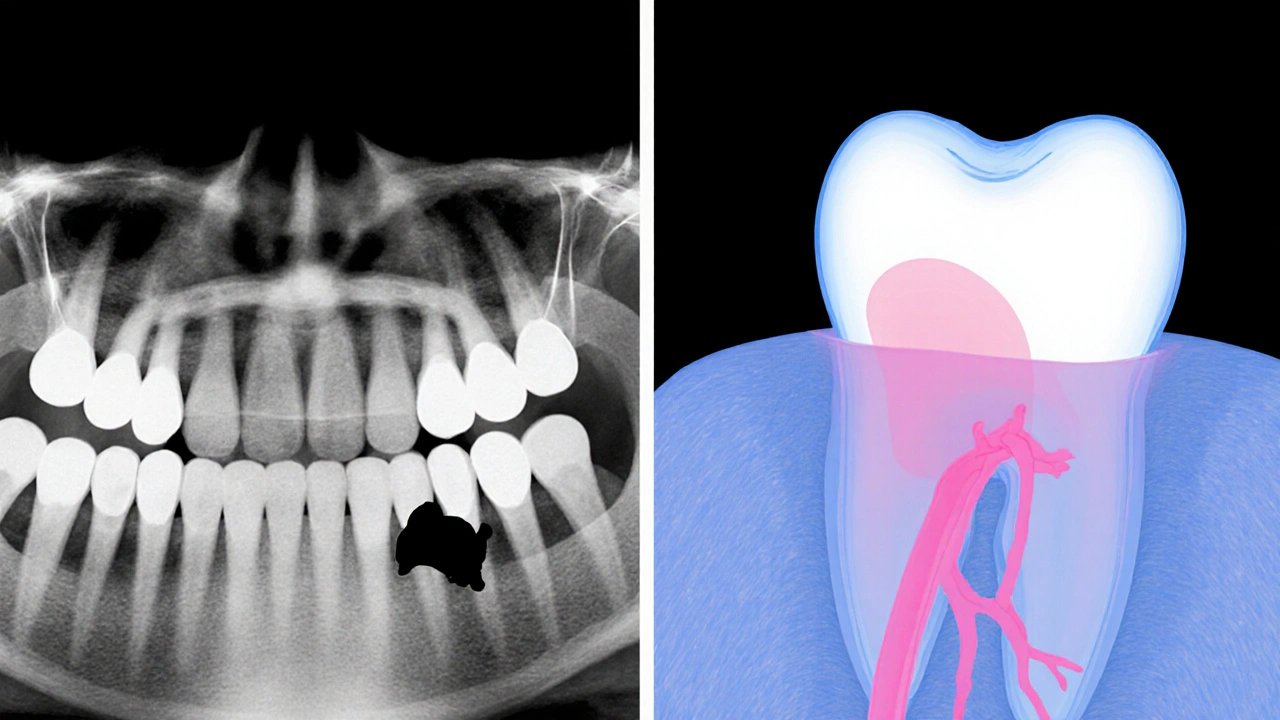

- Rentgen (panoramatický snímek) - ukazuje umístění zubu i případné skryté kořeny.

- CT sken (3‑D zobrazování) - poskytuje detailní pohled na vztah zubu k nervům a vedlejším strukturám.

Rentgen zobrazuje celkový profil zubu v 2D, zatímco CT sken poskytuje detailní 3‑D model, který odhalí přesnou polohu kořene a vztah k nervům.